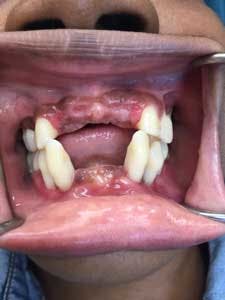

Six months postsurgery, a recommendation was made to the patient to remove the lower incisor teeth—Nos. 23, 24, 25, and 26—due to increased mobility and discomfort upon chewing. A lower anterior temporary partial was provided (figure 3).

Over the following year, a moderate amount of plaque and calculus was observed and home care began to fail. The patient reported difficulty with chewing, and switching to a soft food diet did not seem to be helpful. Periodontal recall maintenance continued on a three-month basis.